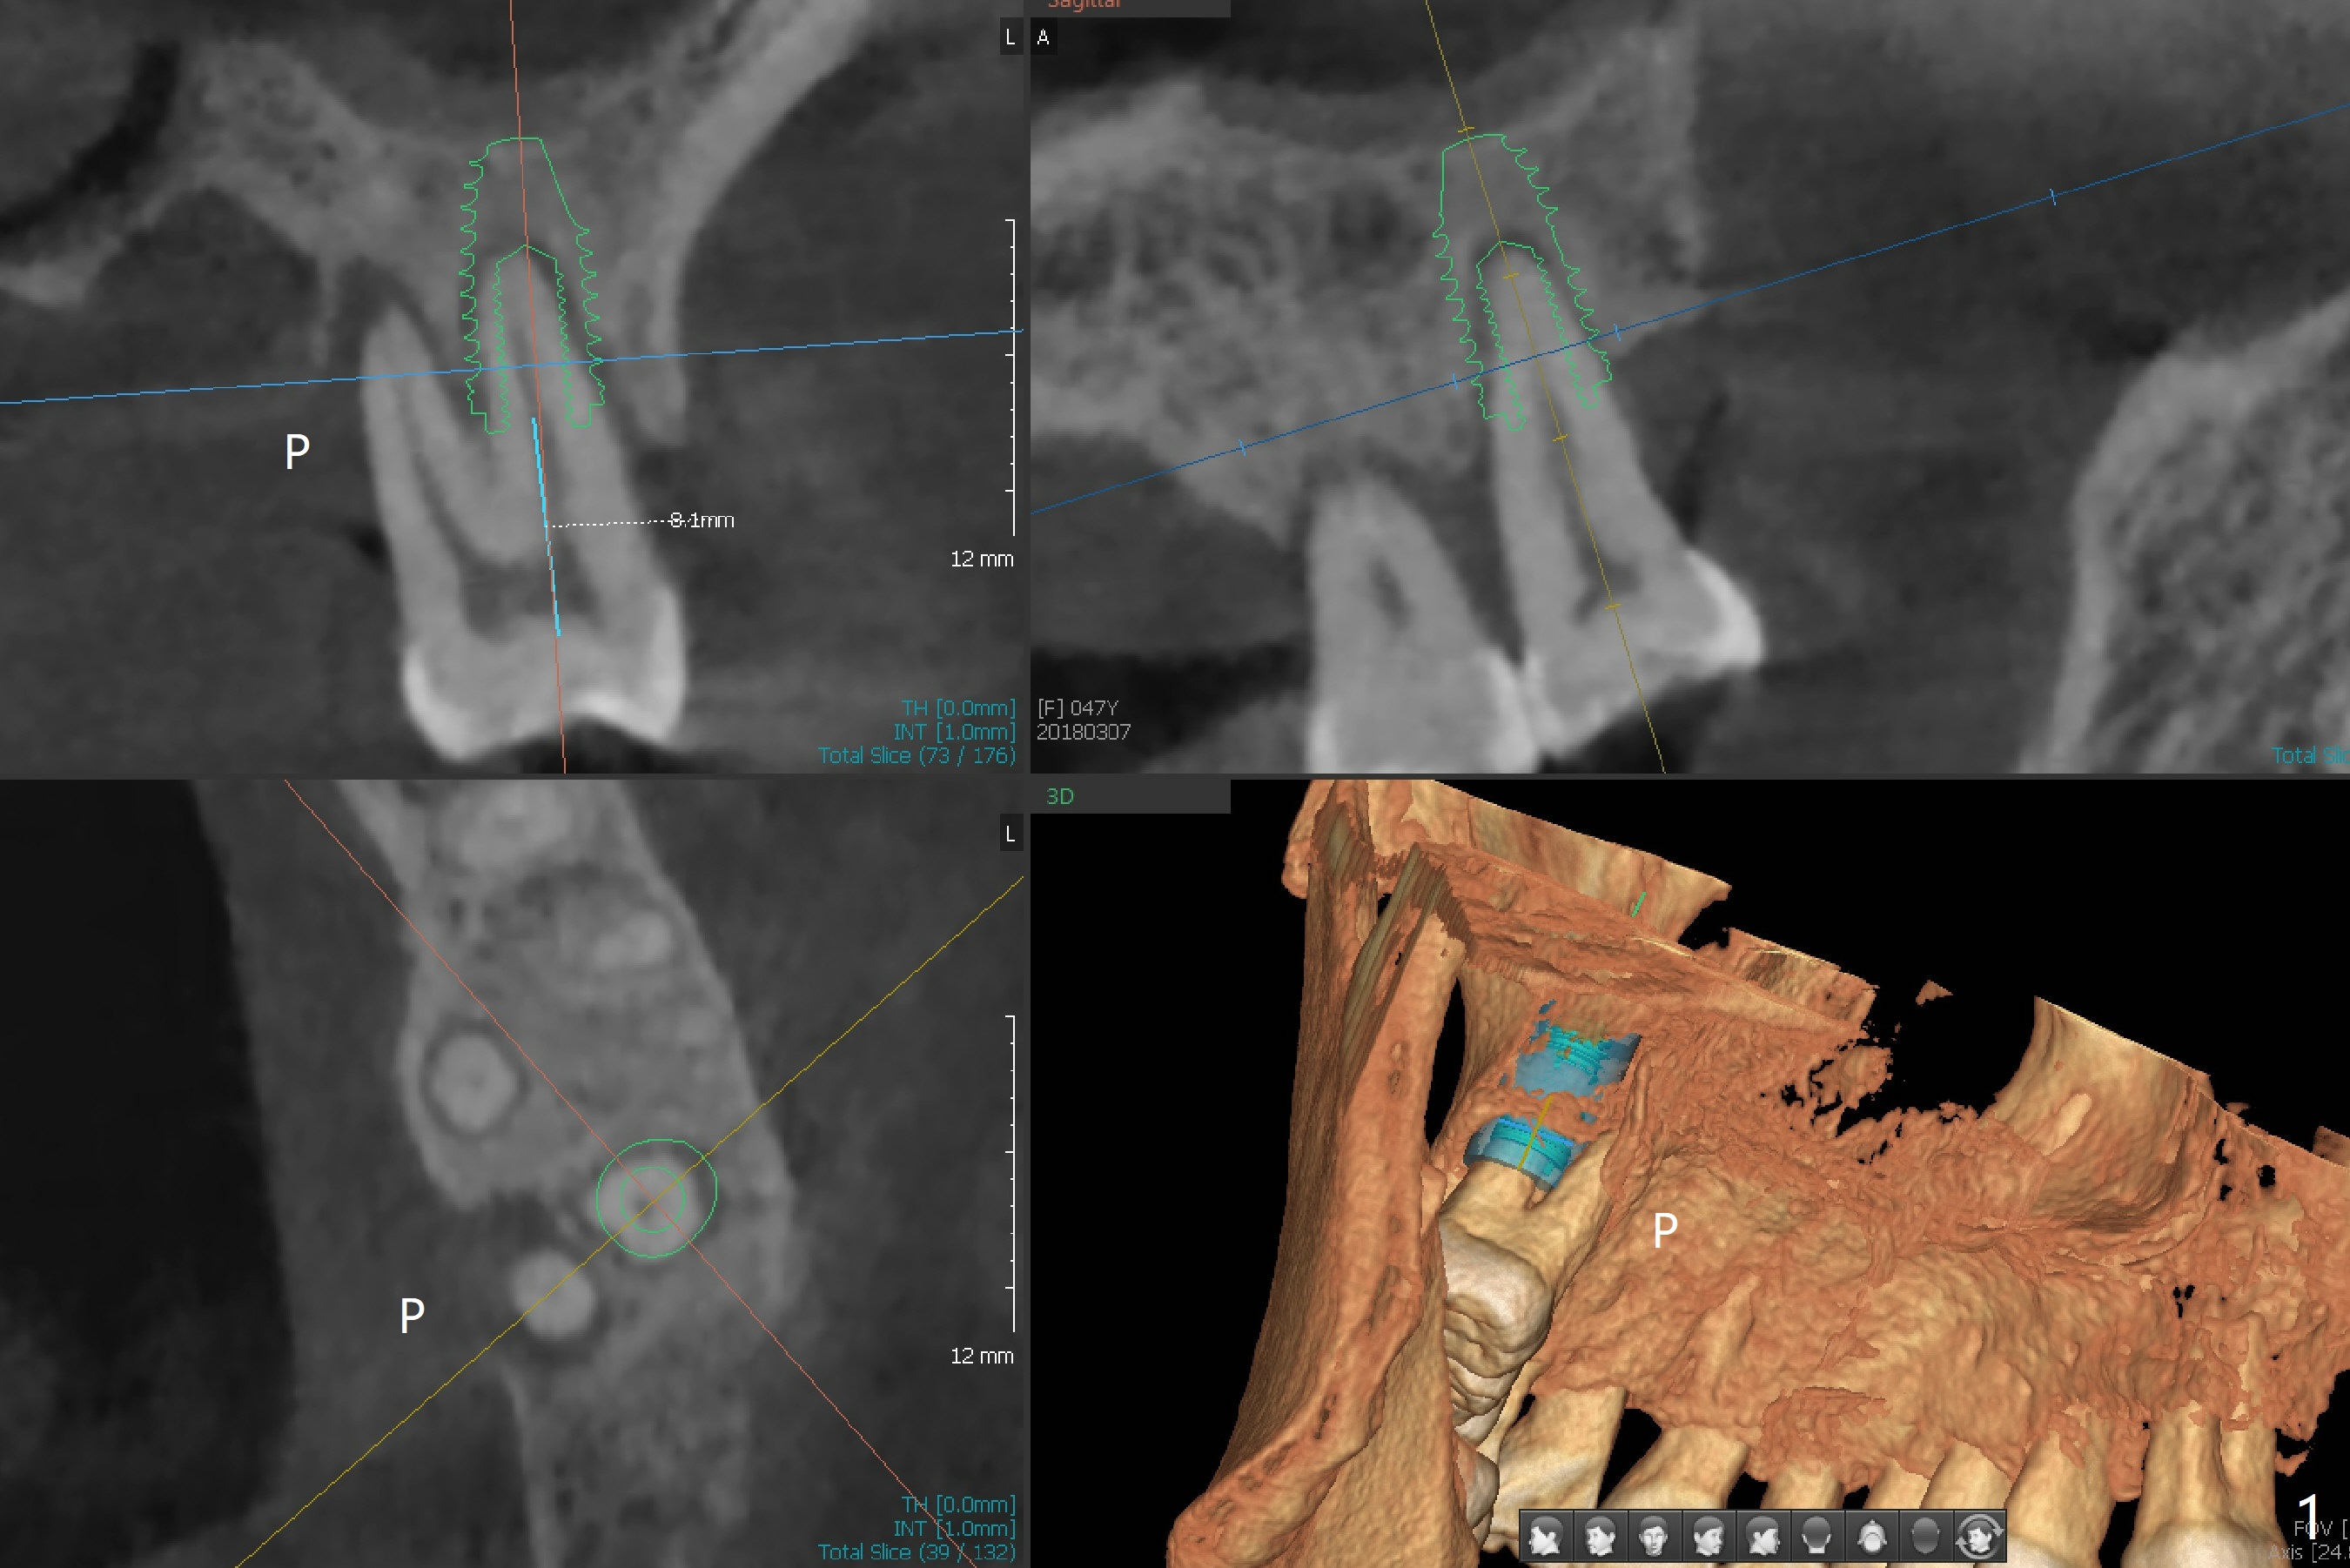

Palatal Bone Loss, Buccal Placement

The 47-year-old woman has sudden palatal (Fig.1: P) periodontal infection (bone loss) at #15 while waiting for surgical guide at #3. A 5x10 mm implant will be in the single buccal socket. The bone height is 3 mm. Start osteotomy with drills with 2 or 3 mm stoppers. Fig.1 shows CT images (UL: coronal; UR: sagittal; LL: axial; LR: 3 D posterior view).